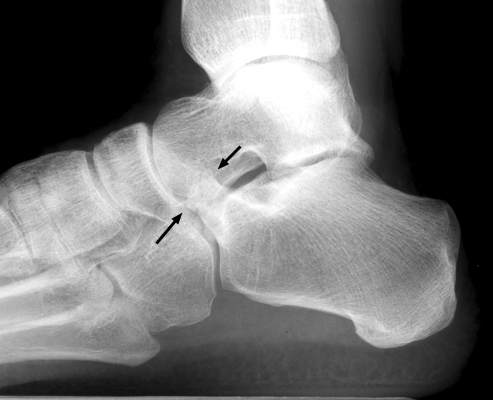

Plain film and CT images of calcaneonavicular coalition. Notice the elongated, tubular like extension of the anterior calcaneus seen on the lateral film; this imagery has been likened to the elongated nose of an anteater. There is abnormal bony fusion of the calcaneus and navicular bones, with the presence of a bony bar extending between these two bones.

- Click on the image for a larger versionALateral foot - Click on the image for a larger versionBCT - Click on the image for a larger versionC